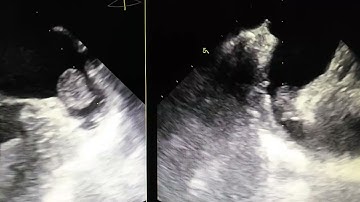

TEE LA appendage thrombus example 2